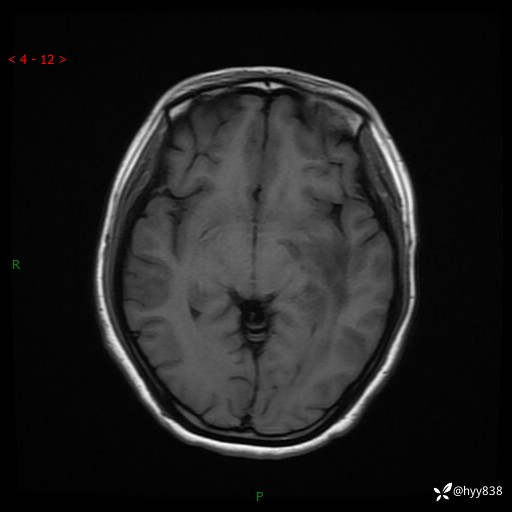

颅脑MRI平扫+增强